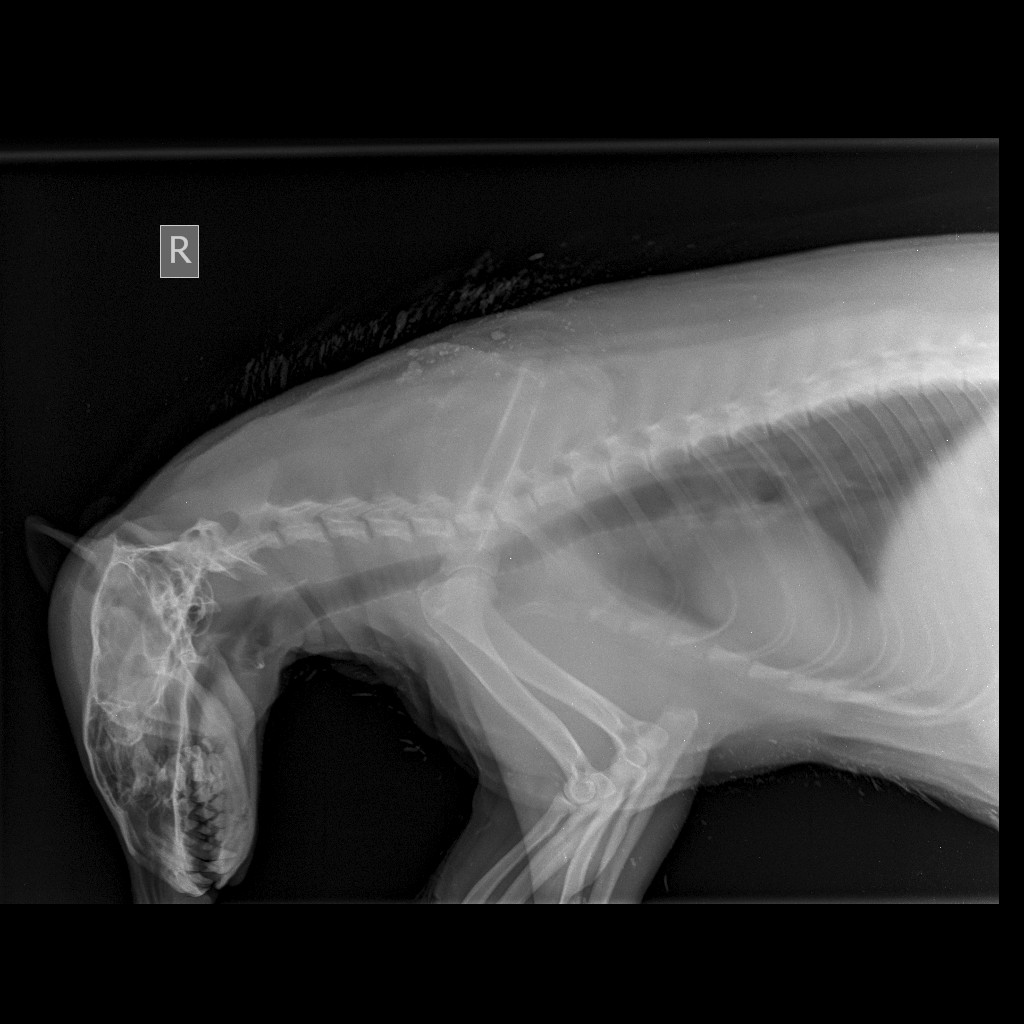

Как рассказали в клинике, барсуку обезболили, сделали УЗИ брюшной полости, обработали от блох и клещей, провели рентгенобследование позвоночника, сделали анализы крови, в том числе на бабезиоз и дали заключение — у барсука обезвоживание, анемия и поражение грудо-поясничного отдела позвоночника неясного генеза, поскольку явных переломов позвоночника по снимкам не выявлено. Причины, по которым зверек пока не пользуется задними лапами, или дифференциальных диагнозов два:

- перелом позвоночника, который не всегда виден на рентгене;

посттравматический спинальный шок.

Для того чтобы определить истинную причину, необходимо сделать МРТ-исследование позвоночника, которое планируют провести сегодня. Сейчас барсуку в клинике проводится дегидратационная терапия, обезболивание и симптоматическая терапия.